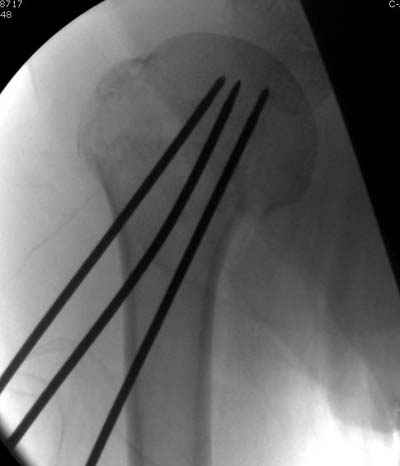

Женя, а как ты водишь спицы, в смысле, как делаешь входное отверстие, и как в него проводишь V-спицу? А то о дна из спиц, та, у которой не дошла до головки одна палочка буквы V, как-то выглядит на рентгенограмме, как будто или через очень большое отверстие введена, или каждая половинка через отдельные отверстия.

Мне кажется, проблема в том, что не все концы спиц зашли в головку, и зашедшие - недостаточно далеко прошли.

Спицы провожу по передней и задней поверхностям плечевой кости через 4,5 мм отверстия на разных уровнях.

Уточни - обе части буквы V вводишь в одно отверстие? А то по снимкам выглядит, что в разные.

V-спица проводится через 4,5 мм отверстие. Видимо, из-за разной длины вторая половина спицы *пролетела* мимо отверстия, что и привело к вторичному смещению костных фрагментов.